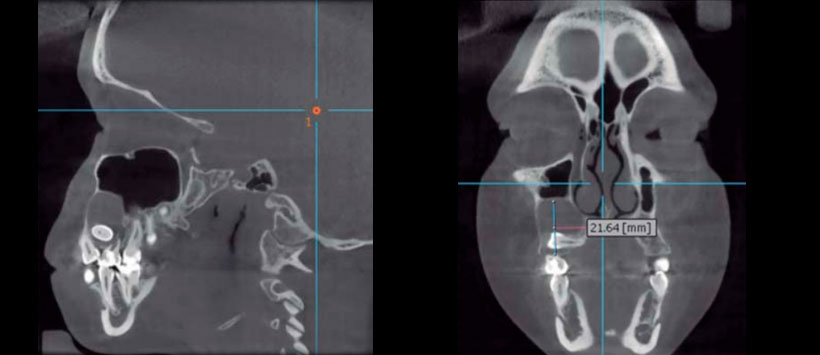

Imagenológicamente en la ortopantomografía se observó una zona radiolúcida unilocular circunscrita bien delimitada, con borde radiopaco bien definido, segundo premolar incluido en posición horizontal. Segundo molar deciduo con tratamiento pulpar. Tomografía de haz cónico: cortes axiales, sagitales, coronales y reconstrucción tridimensional mostraron quiste maxilar derecho de 2.6 cm de diámetro total, ocupando la tercera parte de la capacidad volumétrica de seno maxilar, desplazamiento de la pared anterior de seno maxilar y pared lateral de la fosa nasal derecha (Figuras 4 a 6).